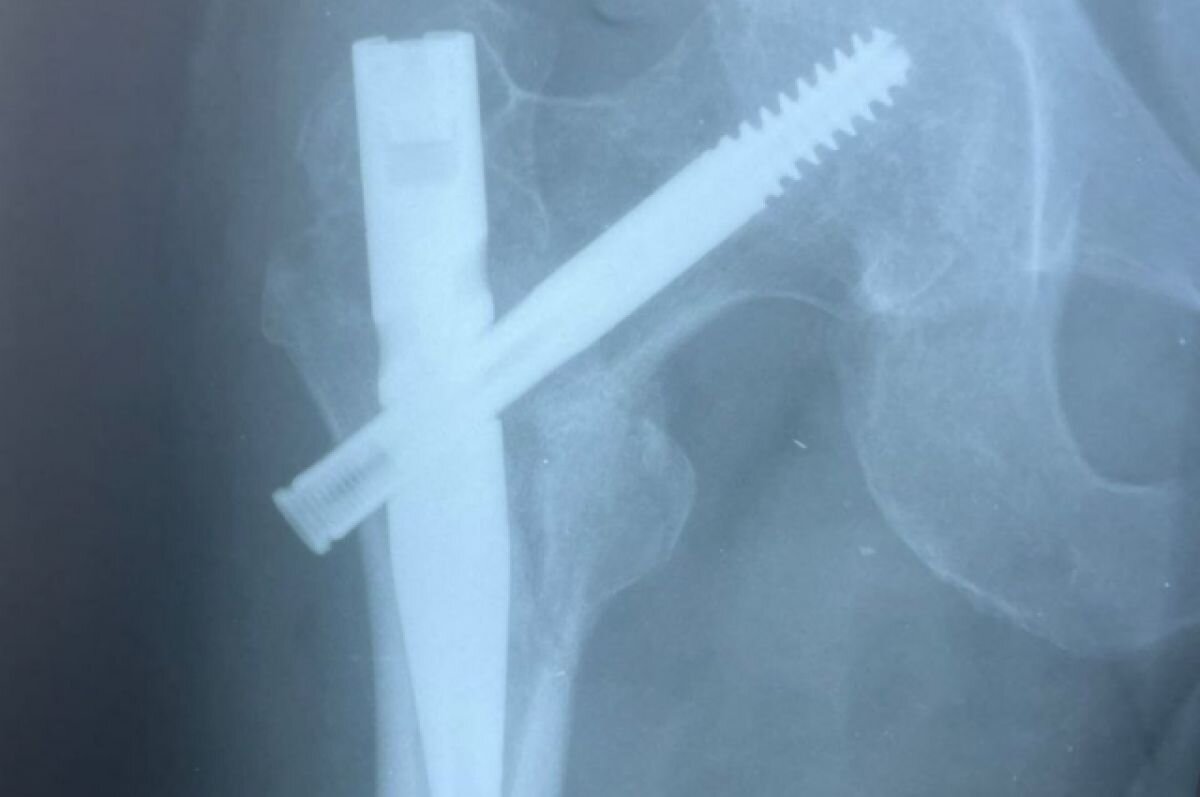

Сотрудники пятигорской больницы, куда мужчина поступил позже, использовали другой метод лечения - БИОС (блокируемый интрамедуллярный остеосинтез). В бедро пациента вставили стержень-фиксатор.

«Технология сокращает срок нахождения в больнице до пяти дней и исключает вторичное смещение костных фрагментов», - рассказал травматолог-ортопед ГКБ Пятигорска Исмаил Ахмедов.